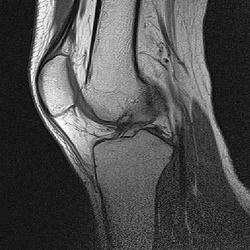

昨日は病院にMRIを撮りにいったんだった。

で、画像をCD-Rに焼かれたのを頂いて帰ったわけです。

まぁ、こんな感じ。

00000012.jpg

まぁ、医者じゃねーから分からんけど。

あ、俺のひざには愉快な奴が居るわ。